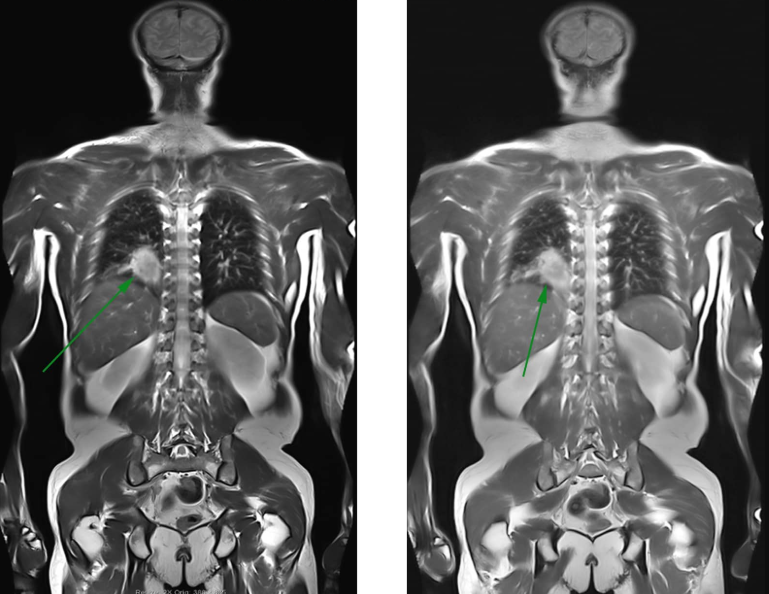

- Lồng ngực: Phát hiện u phổi, u trung thất, hình thái của tim.

- Bệnh ác tính: phát hiện u ở các cơ quan như: phế quản, biểu mô thận, gan,tụy, đại trực tràng, lymphoma, các u xương, mô mềm, ...

- Phát hiện các di căn ung thư đặc biệt ở não, gan, xương, ...

- Giá trị chẩn đoán cao, phát hiện khối u kích thước nhỏ

Hình ảnh chụp cộng hưởng từ (MRI) có độ tương phản cao, chi tiết giải phẫu tốt cho phép phát hiện chính xác các tổn thương hình thái, cấu trúc các bộ phận trong cơ thể. Khả năng tái tạo hình ảnh 3D, có thể phát hiện các khối u có kích thước nhỏ hơn 3mm (bằng 1⁄2 hạt đỗ), chụp mạch máu không cần tiêm chất tương phản. Đặc biệt có thể định hướng được u lành và u ác tính.